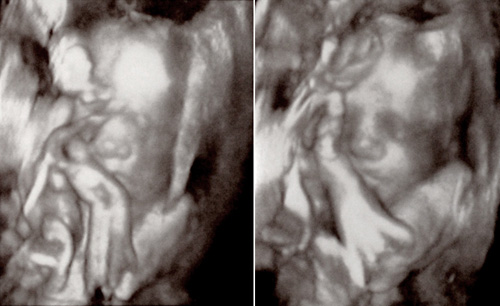

She is however breech! I was a bit shocked to hear that because her feet are always up at my ribs on my right side. And it is indeed her feet up there… she has her feet over her head! We saw her grabbing her feet with her hands. And it’s funny because she was in that same position during my level 2 ultrasound 10 weeks ago, feet over head. How bizarre they are in there! So I think this is my first breech baby. Devin was transverse up until sometime in the third trimester when he went head-down. Kate was head-down from the start and never moved, head buried in my pelvis against my placenta preventing them from getting good measurements and pictures. I asked the midwife how common it was for them to be breech at this stage and she waved it off with a “Don’t even worry about it.” She said if she’s still breech at 36 weeks I can start doing inversions, but she’s not worried about it at all, there’s lots of time to flip.